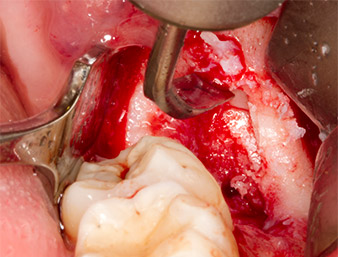

Sous bloc nerveux et anesthésie locale, le site d’intervention est ouvert et les tissus mous sont exposés afin d’accéder à la zone rétromolaire buccale (Fig. 3).

Le tissu recouvrant le reste radiculaire n’est pas entièrement ossifié et est essentiellement constitué de tissu de granulation modifié par l'inflammation (Fig. 4).